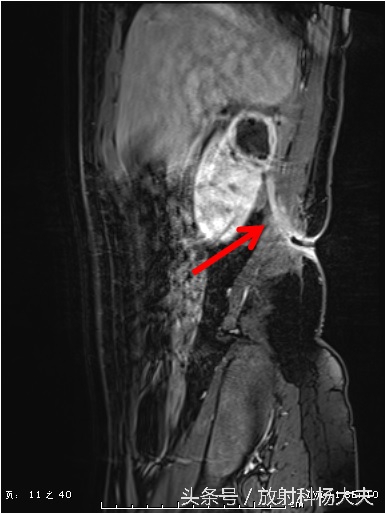

终于搞清楚了,原来一个月前的腰痛,是肾脏的脓肿,而且MRI上还能清晰的显示脓肿破口的位置,下图中黄箭所示(红箭为脓肿)。

还有那弯曲的窦道。